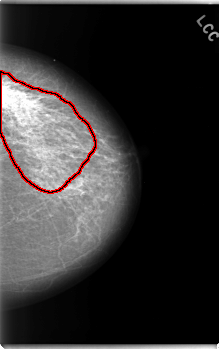

C_0020_1.LEFT_CC

LEFT_CC LINES 5928 PIXELS_PER_LINE 3712 BITS_PER_PIXEL 12 RESOLUTION 50 OVERLAY

FILE: C_0020_1.LEFT_CC.OVERLAY

TOTAL_ABNORMALITIES 1

ABNORMALITY 1

LESION_TYPE CALCIFICATION TYPE PLEOMORPHIC DISTRIBUTION REGIONAL

ASSESSMENT 4

SUBTLETY 2

PATHOLOGY MALIGNANT

TOTAL_OUTLINES 1

BOUNDARY